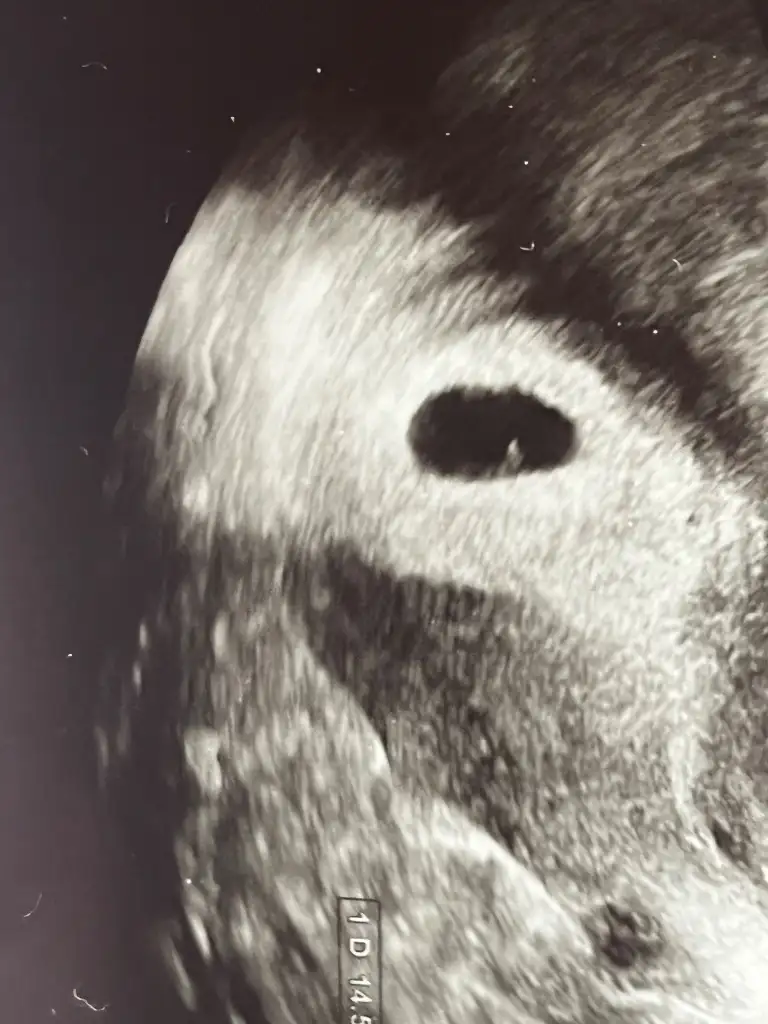

Merhaba canım 5 haftalık 4 küsür mmdi içi boştu benimde. Bugün gittim 6+4 14.53mm haftaya kalp atışı için çağırdıSelam kızlar bir sorum olacak 5+1 de doktora gittim sadece kese vardı içi boş ve büyüklüğü 4 küsür mm çıktı 2 hafta sonra gel dedi. Kalp atışlarını ne zaman duydunuz siz ve 5 haftalıkken keseniz kaç mm di normal olması gereken boyut nedir

Senin 6+4 haftaya çağırmış ben tam 6+0 olmama rağmen bebeği görmedim bebeğin olması lazımdı diyo haftaya kalp atışı diyor olması lazımdı ona göre gel dedi pazartesi gene moralimi bozarsa doktor değişikliği yapayım zaten doktor yok asistanlar bakıyorMerhaba canım 5 haftalık 4 küsür mmdi içi boştu benimde. Bugün gittim 6+4 14.53mm haftaya kalp atışı için çağırdı

Normal o zaman ya insan endişe ediyorMerhaba canım 5 haftalık 4 küsür mmdi içi boştu benimde. Bugün gittim 6+4 14.53mm haftaya kalp atışı için çağırdı

Yolk saç gözükmüş müydü 6 haftalıkkenMerhaba canım 5 haftalık 4 küsür mmdi içi boştu benimde. Bugün gittim 6+4 14.53mm haftaya kalp atışı için çağırdı